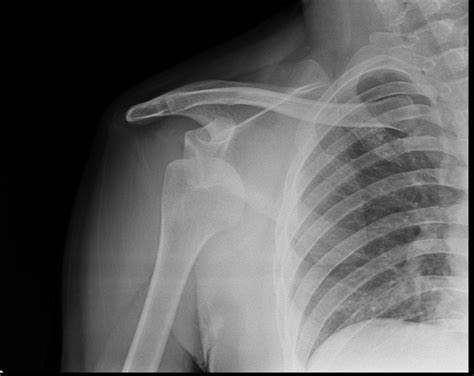

What type of shoulder dislocation does this x-ray show? (AP view)

Anterior dislocation

Typical X-ray findings in anterior shoulder dislocation include: